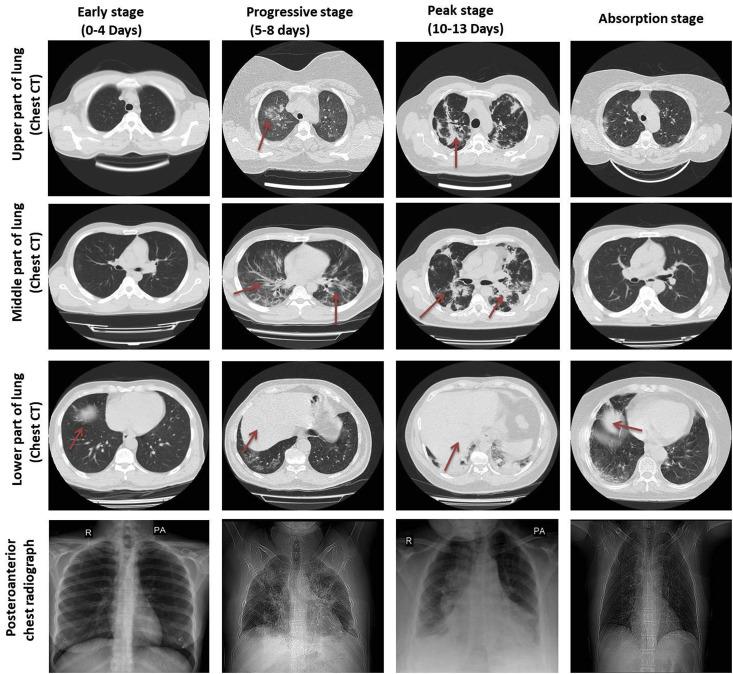

新型冠状病毒肺炎(COVID-19)的诊断与治疗:实验室、PCR 及胸部 CT 影像学表现。

Diagnosis and treatment of coronavirus disease 2019 (COVID-19): Laboratory, PCR, and chest CT imaging findings.